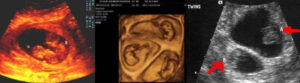

Наличие на УЗИ двойни устанавливается по прослушиванию (характерному бульканью) биения двух сердец, двух полых оболочек (околоплодных пузырей) с амниотической жидкостью и двух провизорных органов (плацент). Виды возможного развития малышей в утробе определяют согласно плацентообразующему органу – хориону и околоплодному пузырю – амниону.

- Дихориальная диамниотическая. Локализация каждого эмбриона определена персональным «детским местом» (плацентой) и амниотическим пузырем. При таком развитии малыши, как правило, разнояйцевые. Двойню видно уже при проведении первого скрининга, начиная с 5–6 недели вынашивания.

- Монохорильная диамниотическая. Эмбрионы располагаются в разных амниотических оболочках, объединенных одним «детским местом». Такую двойню можно увидеть примерно на 9–11 неделе.

- Монохориальная моноамниотическая. Как правило, такую однояйцевую двойню, на УЗИ видно только при втором скрининге. Будущие дети соединены общим амниотическим пузырем и общей плацентой. Это наиболее проблемный вид двухэмбриональной беременности, который тяжело выносить без осложнений.

- Бихориальная биамниотическая двойня – оба зародыша обернуты отдельными плацентой и амниотической оболочкой. Может быть развитие двуяйцевых и однояйцевых двойняшек, если дробление одной яйцеклетки будет через три дня после зачатия.

- Монохориальная биамниотическая – эмбрионы разделены двумя амниотическими оболочками, но находятся в одной плаценте, перегородка между плодами имеет два слоя. Такая разновидность двойняшек будет именно однояйцевой при дроблении яйцеклетки в промежутке 3 и 8 дня после зачатия.

- Монохориальная моноамниотическая – одна плацента и одна амниотическая оболочка для двух плодов, межплодовая оболочка не присутствует. Эта двойня – только однояйцевая, развивается при дроблении одной яйцеклетки с 8 по 13 день после зачатия.